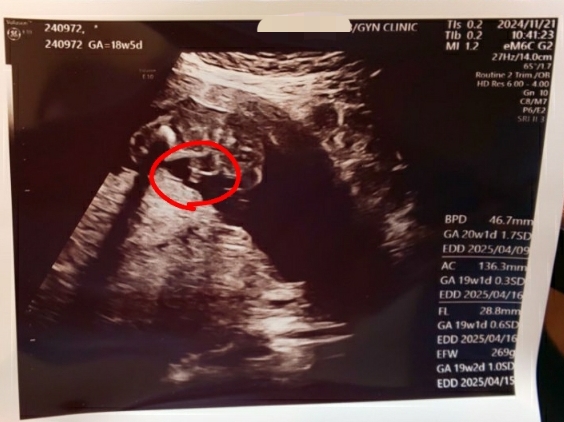

※エコー写真載せてます※

先生から「らららさん、赤ちゃんの性別知りたい~?」と聞かれたのですかさずYes!と答えた私。笑 赤ちゃんと子宮の大きさを一通り測定して、我が子は平均よりも少し大きめに育っているとのことでした。今18w5dですが19wぐらい育っているらしいです。決してバランスの良い食事とは言えず、好きな物食べてただけですが順調に育ってて安心しました… ちなみに私の体重は2キロ増量してました!

ここなんだけど何かついてるのわかる?

これは…もしかしておちんでは…!?

そう!男の子だね~

我が子、メンズと判明!!

4Dのエコーでは真後ろを向いていて顔を見ることはできませんでした笑 耳や背骨も見えています。2Dエコーの時は腕を動かしたり脚をジタバタさせていました。18週に入ってからなんとなく胎動がわかるようになってきて、特に私が喋るとお腹の中がニョロニョロ動くようになりました。コールセンター勤務なので部下に指導したり、私が上席対応でお客様と直接お話することが多いのですが、その間お腹がもぞもぞ動いています笑 仰向けで寝てる時は特に胎動がわかりやすいです。